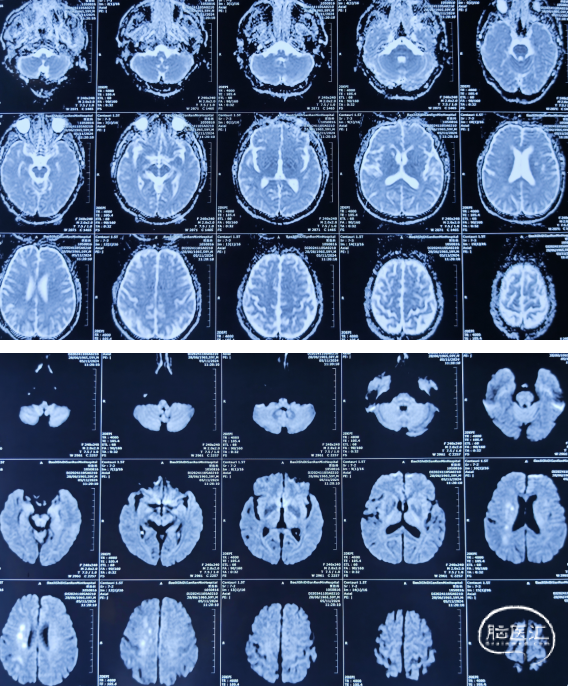

PWI(2024.11.07)

DSA造影(2024.11.07)

右侧颈内动脉起始段闭塞,动脉晚期可见颈动脉颅内段浅淡显影。

前交通动脉开放,右侧大脑中动脉显影良好。

右侧后交通动脉开放,右侧颈动脉颅内段浅淡显影。

HR-MRI(2024.11.09)

右侧颈内动脉全段管壁不均匀性增厚,腔内见多发混杂信号影,管腔显著狭窄、闭塞。增强扫描管壁不均匀强化,管腔内部分成分强化。